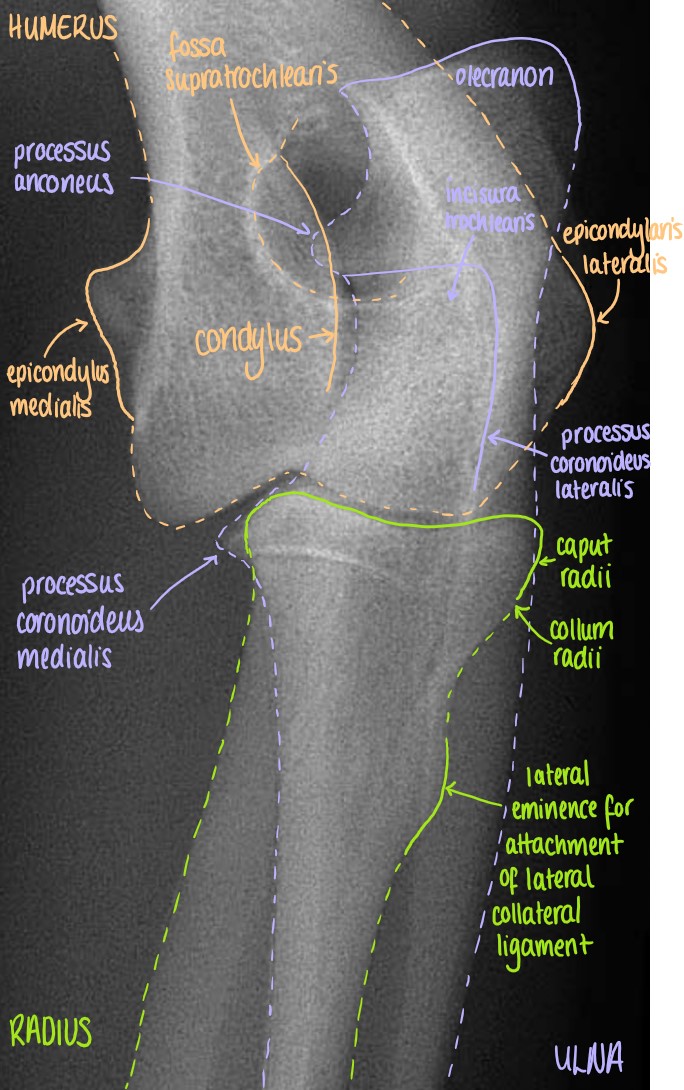

Articulatio Cubiti